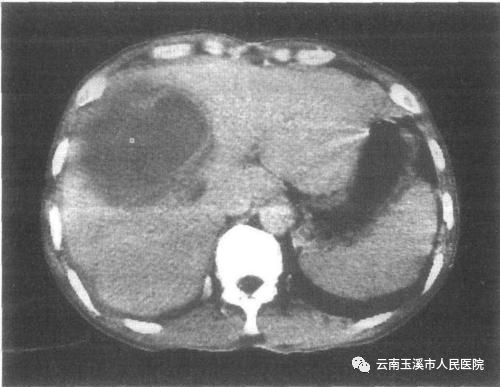

3.如脓腔较大,可先切开皮肤约1cm长的切口,再将套管针刺入脓腔,经外套管向脓腔内放入一条多孔引流管,拔出套管后,以缝线将引流管固定于皮肤上,管端接无菌引流瓶,以备冲洗引流。

经皮经肝穿刺置管引流术术中